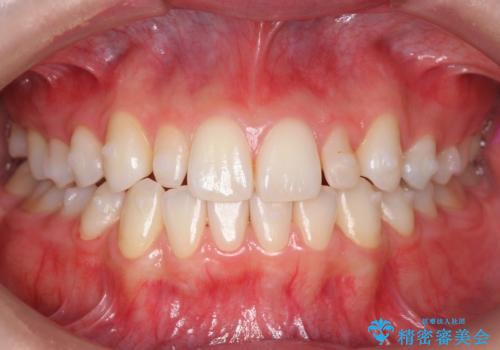

- 前歯のがたつきと小さな歯の形を治したいと来院。

前から2番目の歯が小さく、細くとがった形になっていました。

大きくしようにも、幅が少ない上に、また、内側に入ってしまっているため、矯正治療で前歯を並べてからセラミックでかぶせることにしました。

いきなりセラミックでかぶせるよりも手間をかけた分、自然な仕上がりになっています。